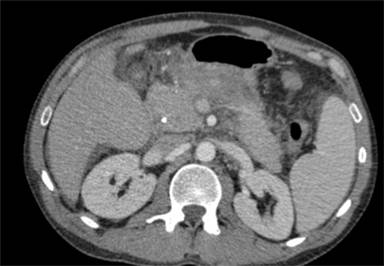

Endoscopic retrograde cholangiopancreatography (ERCP) is a fundamental tool in the management of in magnetic resonance cholangiopancreatography (MRCP) and endoscopic ultrasound (EUS), ERCP has biliary and pancreatic diseases. With technological advances evolved into a therapeutic rather than diagnostic procedure. Nevertheless, these procedures carry significant risk, with post-ERCP pancreatitis (PEP) being the most frequent and dreaded of these [1] (Figure 1). The incidence of pancreatitis after ERCP is approximately 5-10% [2-4], but exceeds 30% in certain high-risk groups [5]. It is essential for the modern advanced endoscopist to recognize PEP, understand the risk factors, measures for prevention, and the necessary steps in management. The primary aim of this article will be to review the recent advances in prevention and management of PEP.

Figure 1. Computed tomography reveals peri-pancreatic fluid and stranding two days after ERCP in 40-year-old man with severe epigastric pain and fevers. |